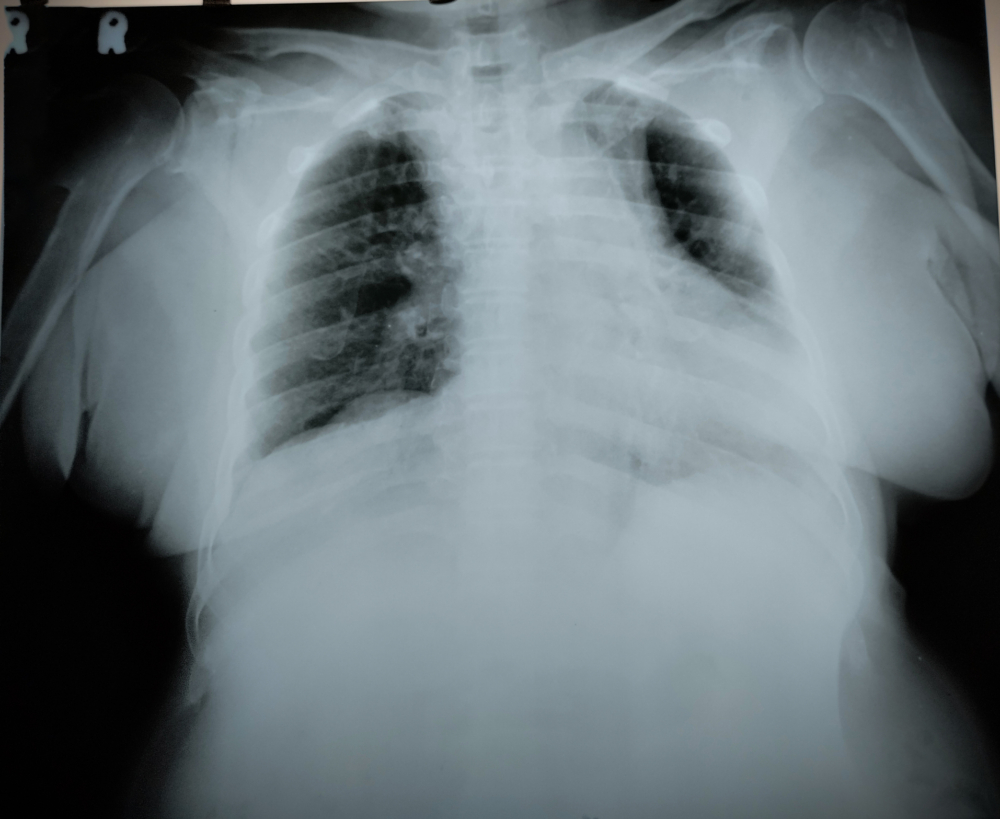

長期病患、患上癌症如肺癌,或受到感染均是引起肺積水的常見原因。肺積水症狀包括呼吸急促,胸部疼痛(特別在咳嗽或深呼吸時),咳嗽及發燒。 醫生會透過病歷、臨床檢查及胸部X光去確認診斷肺積水。

- 胸腔穿刺:醫生會使用針頭或導管將積聚在胸腔內的積液抽取出來,這是一個安全且有效的過程,亦可快速的緩解肺積水症狀。在胸腔穿刺的過程中,醫生可以通過超聲波或X光進行引導,以確保準確無誤的把積液順利抽出。